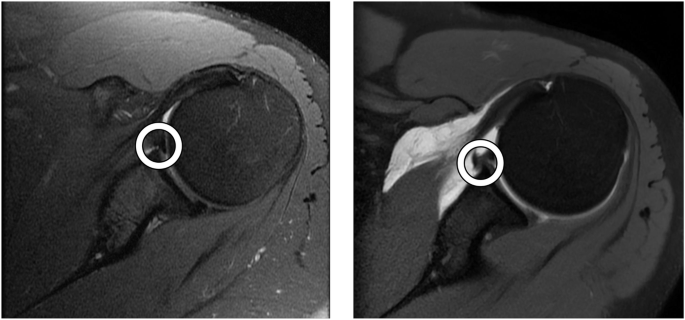

Grad-CAM33 visualizations highlight regions relevant to a model’s predictions. Figure 5 presents Grad-CAM heatmap visualizations for the axial view for four representative cases: an MRA without a tear, an MRA with a Bankart lesion, a standard MRI without a tear, and a standard MRI with a Bankart lesion. For all heatmaps, annotations highlight the anterior labrum, placed by a shoulder/elbow fellowship-trained orthopedic surgeon. The model attended to the relevant portions of the image, as determined by the surgeon, on all four cases.

Cases with and without Bankart lesions are presented. The model correctly classified all four cases. White circles highlight the anterior labrum (the region of interest), annotated by a shoulder/elbow fellowship-trained orthopedic surgeon. Heatmaps indicate regions most influential to the model’s prediction, with warmer colors (red/yellow) signifying higher relevance.

The Grad-CAM visualizations in Fig. 5 for the MRAs demonstrate focused activation within the anterior labrum for both the no-tear case and Bankart lesion case. For the no-tear MRA, the area of highest activation is in the anterior-inferior labrum region, but there is an additional lesser area of activation near the posterior

labrum. In the Bankart lesion case, there is strong overlap between the activation and the surgeon-annotated region highlighting the tear, likely indicating that the model successfully identified the pathological features associated with the tear. For the standard MRIs, the Grad-CAM visualizations show less localized activation compared to MRAs, with several peripheral areas of minor activation near the image edges in both cases. This reduced specificity in the activation maps may result from the lower visual clarity of labral structures on standard MRIs due to the lack of intra-articular contrast. Additionally, as noted in Table 3, the standard MRIs had a significantly lower percentage of 3.0 T exams (i.e. higher proportion of lower quality 1.5 T exams)—suggesting that the lower average image quality in the standard MRI group may also have contributed to the less focused heatmap. Although the standard MRI dataset was larger overall (335 MRIs vs. 251 MRAs), it contained far fewer positive cases (8.6% vs. 31.9%), creating substantial class imbalance. This imbalance likely limited the model’s ability to learn localized features, leading to more diffuse activations. The broader activations likely reflect a combination of these factors, underscoring the need for cautious interpretation. For the no-tear standard MRI case, the heatmap shows the highest activation in the anterior labrum, suggesting that the model still prioritizes this region as a key diagnostic feature, even in the absence of pathology. For the Bankart lesion case, the anterior labrum remains the area of highest activation, but the heatmap also strongly highlights additional regions within the joint space. Unlike for the MRA, the annotating surgeon noted no obvious tear characteristics for the standard MRI with a Bankart lesion. Consequently, the additional highlighted regions in the model’s heatmap may reflect subtle imaging cues associated with the tear that are not easily discernible to human observers. This suggests that the model may capture features indicative of the tear that are challenging for radiologists or surgeons to detect on standard MRIs due to the lack of intra-articular contrast.